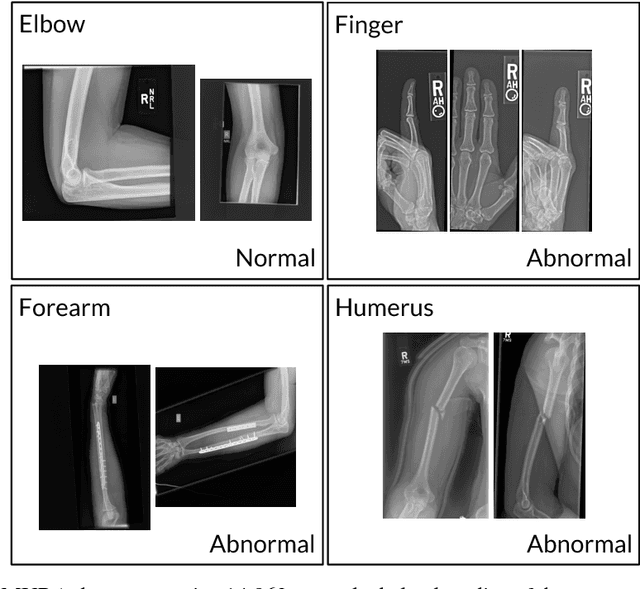

Abstract:We introduce MURA, a large dataset of musculoskeletal radiographs containing 40,561 images from 14,863 studies, where each study is manually labeled by radiologists as either normal or abnormal. To evaluate models robustly and to get an estimate of radiologist performance, we collect additional labels from six board-certified Stanford radiologists on the test set, consisting of 207 musculoskeletal studies. On this test set, the majority vote of a group of three radiologists serves as gold standard. We train a 169-layer DenseNet baseline model to detect and localize abnormalities. Our model achieves an AUROC of 0.929, with an operating point of 0.815 sensitivity and 0.887 specificity. We compare our model and radiologists on the Cohen's kappa statistic, which expresses the agreement of our model and of each radiologist with the gold standard. Model performance is comparable to the best radiologist performance in detecting abnormalities on finger and wrist studies. However, model performance is lower than best radiologist performance in detecting abnormalities on elbow, forearm, hand, humerus, and shoulder studies. We believe that the task is a good challenge for future research. To encourage advances, we have made our dataset freely available at https://stanfordmlgroup.github.io/competitions/mura .